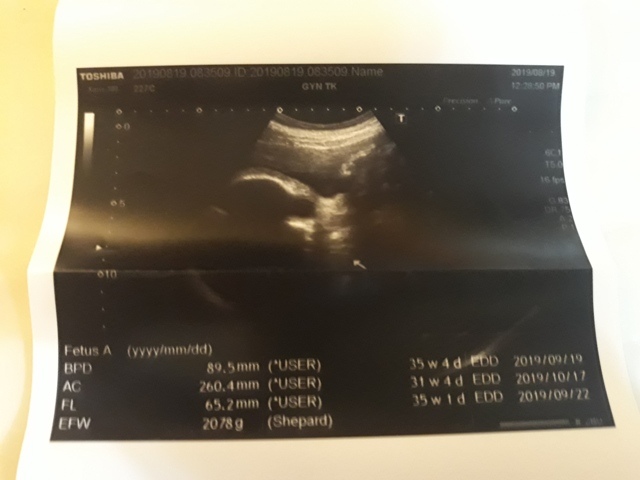

| 仙人掌(2019/08/19)的真心話 星期一 天氣晴 編號19-220 |

近十次產檢資料統計(5月22日是高層次超音波)↓

| 2019年08月19日 | 89.5mm(17%) | 260.4mm(-9%) | 65.2mm(-1%) | 2078g (-1%) | 未量測 |

| BPD:胎兒頭骨橫徑 AC:胎兒腹圍的長度 FL:胎兒大腿骨的長度 EFW:胎兒的體重 括弧內百分比為較上次產檢的成長比例 | |||||